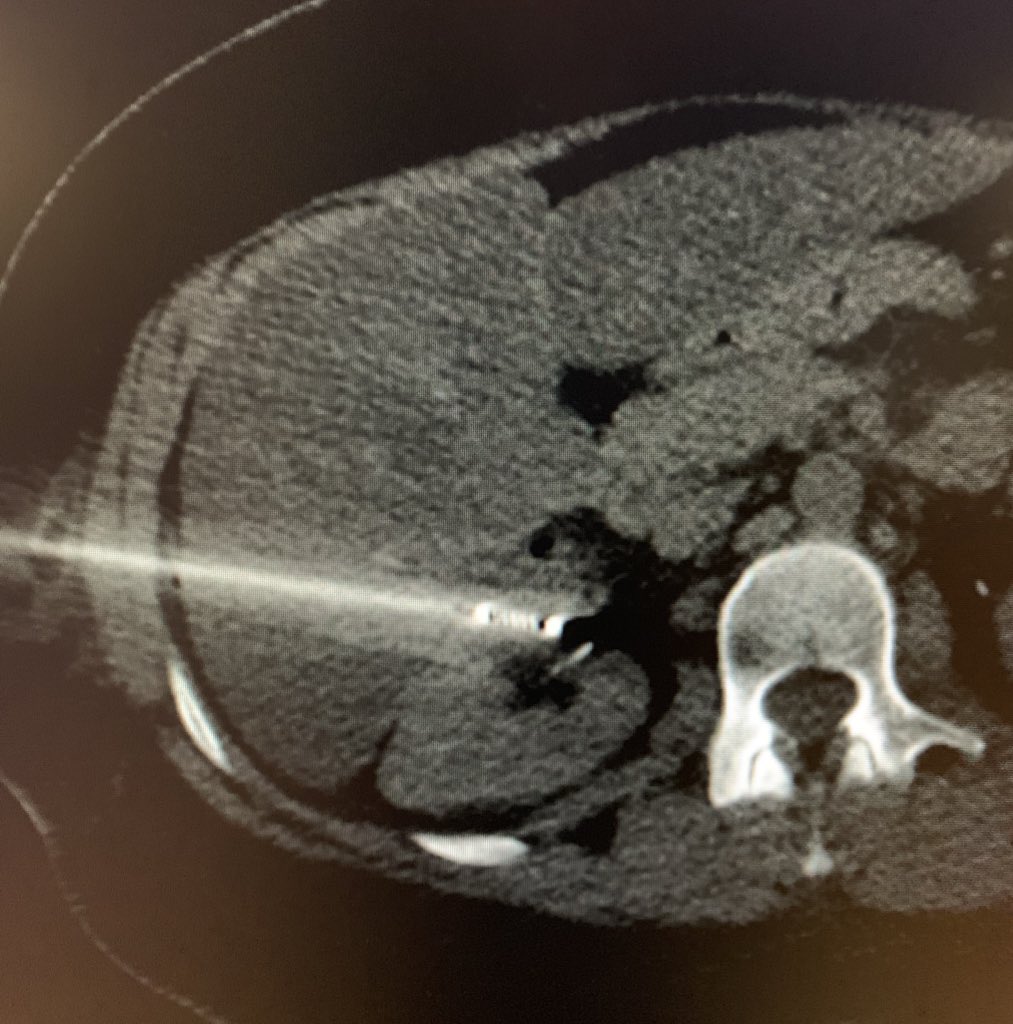

How would you ablate this renal cell carcinoma?

@BWHRadEdu@SIRspecialists@SIRRFS#iRad#ablation#cryoablation pic.twitter.com/6c8YEyFaVo

Transhepatic

@BTGIO#cryoablation of an anterior biopsy-proven clear cell RCC in a young patient. Referred from urology after lengthy multidisciplinary discussion re: surgical options.#iRad#IRonc#TeamWorkpic.twitter.com/LzqA4H0vGb